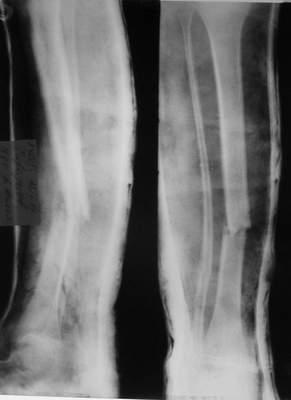

Так как речь зашла непосредственно о травме, см этапные

снимки. Как все было

Фиксация

|

в гипсе